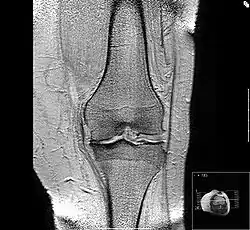

MRI of osteoarthritis in the knee, with characteristic narrowing of the joint space -

Diagnosis is made with reasonable certainty based on history and clinical examination.[52][53] X-rays may confirm the diagnosis. The typical changes seen on X-ray include: joint space narrowing, subchondral sclerosis (increased bone formation around the joint), subchondral cyst formation, and osteophytes.[54] Plain films may not correlate with the findings on physical examination or with the degree of pain.[55]